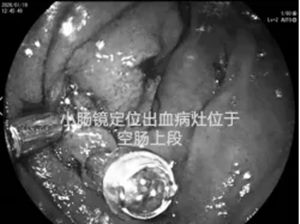

此时,消化内科二病区刘谦主任与于政洋医生作出关键判断:出血点极有可能位于占消化道全长70%、却常规检查难以探及的"盲区"——小肠。

团队果断启用诊断"利器"——小肠镜。它深入探查的能力,如同为黑暗的小肠点亮了一盏探照灯,精准捕获了那个直径2cm、正在持续渗血的间质瘤,实现了"定位病变"的关键突破。